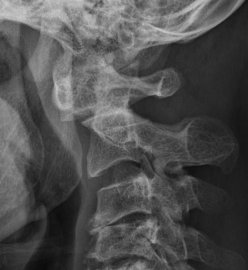

Subaxial Subluxation (SAS)

Definition

Anterior subluxation of one vertebral body on another

Results in spinal stenosis

Diagnosis

A. Instability on Flexion / Extension views

- > 3mm

- > 11o

Anterior subluxation of C3 on C4

B. Space available for cord / SAC

- subaxial canal diameter on lateral

- < 13 mm high incidence neurology

Pathology

Facet erosions / ligament incompetence

May see at multiple levels with stepladder type deformity & kyphosis